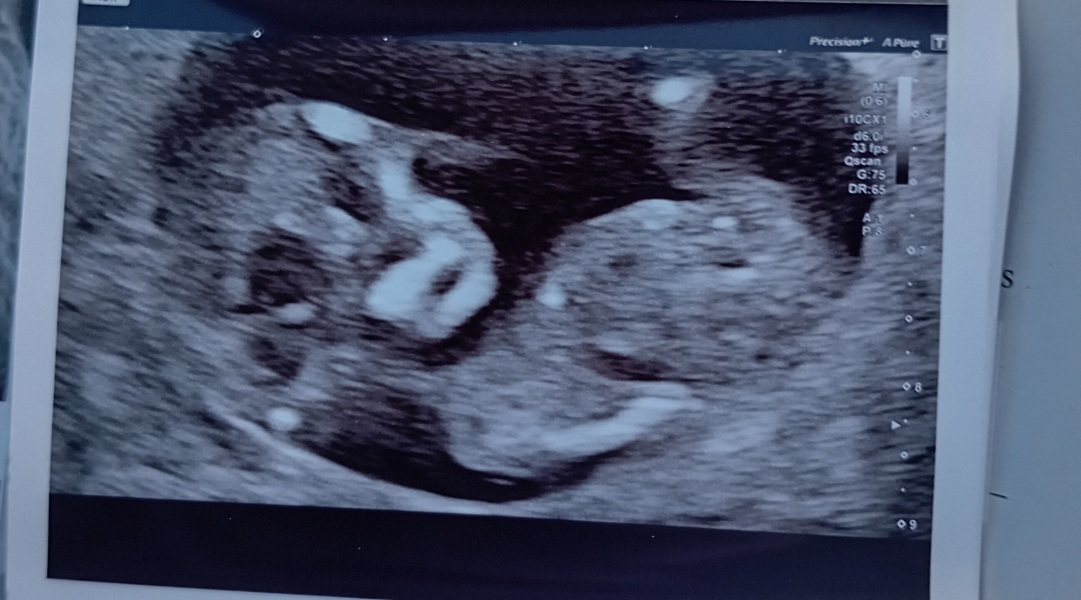

Wanttobeamommy · 07/04/2025 17:48

Update had another scan today, 12 weeks 💙💖

Any ideas?

Nub theory guesses

mangosmoothie123 · 07/04/2025 17:48

Boy

AliBaliBee1234 · 07/04/2025 17:50

No nub on this one 🥰

Although I feel like if it was a girl it would probably be visible at this angle. I'm going to guess boy.

Congrats on a healthy baba!

mangosmoothie123 · 07/04/2025 17:52

Do you have another pic, there’s no visible nub on this one, however skull theory would suggest boy to me here. Your original photos look like boy nub to me too